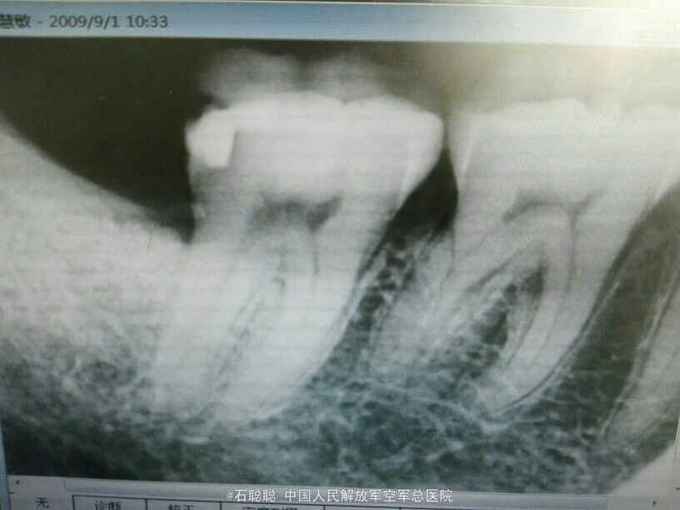

检查:右下7远中合面银汞充填体,边缘发黑,探针可探入,探痛+,冷+,叩痛-,不松动,牙龈未见异常 根尖片:右下7远中冠方见高密度充填影像,下方密度减低,近髓

诊断:右下7牙髓炎 治疗计划:右下7RCT后冠修复 处置:右下7“利多卡因”局麻下开髓,揭顶,探及近颊、近舌、远中3和根管口,略疏通,见血性渗出,冲洗,干燥,置失活剂,氧化锌暂封 一周后复诊:去除右下7暂封,测工作长度,近舌=19mm,扩大至30#,近颊=远中=18mm,扩大至35#,冲洗,干燥根管及髓腔,置CP棉球,氧化锌暂封 一周后复诊: 查:右下7叩痛-,不松动,氧化锌完整在位 处:去除右下7氧化锌暂封,试主尖,冷侧压充填,氧化锌暂封,建议一周后修复